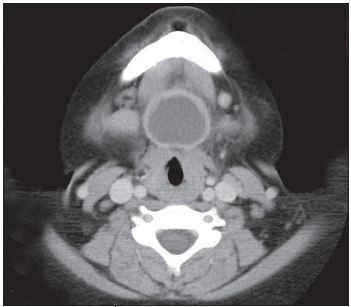

Shashi Sahai, MD; Mark Borkin, MD; Deepak M. Kamat, MD, PhD

A 9-year-old Hispanic boy presented with submental swelling and dysphagia.